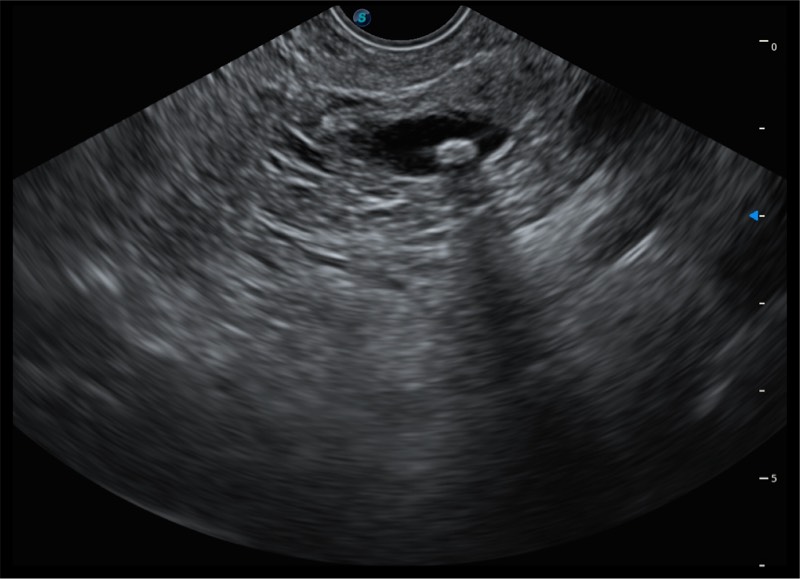

搭载百万级CMOS成像技术

及自主研发凸阵换能器,

可呈现优质的内镜和超声画面

基于二十年的超声技术积累,玖鼎集团提供了最新一代的独立超声主机,在提供高质量图像的同时满足多学科使用。具备常见多普勒技术并提供弹性成像、声学造影等高端影像技术。新一代传感器具有更强的抗干扰能力并减少图像伪影。

4-12MHZ宽频输出